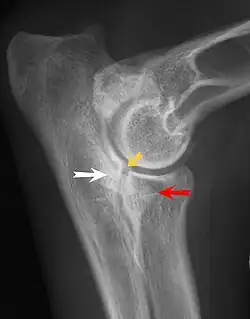

Most primary lesions are related to osteochondrosis, a disease of the joint cartilage, and osteochondritis dissecans (OCD), the separation of a flap of cartilage on the joint surface. Other common causes of elbow dysplasia include an ununited anconeal process (UAP) and fragmented or ununited medial coronoid process (FCP or FMCP).[1]

UAP is caused by a separation from the ulna of the ossification center of the anconeal process.[7] FMCP is caused by a failure of the coronoid process to unite with the ulna.